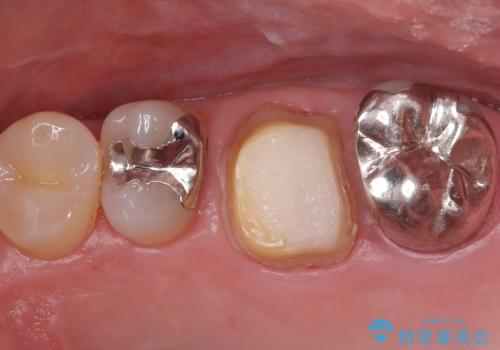

- 患者様は、他院で根管治療を受けていたが、なかなか治らず、より精密な治療を希望して当院を受診されました。マイクロスコープを使用して詳しく診断したところ、上顎第一大臼歯(6番)のMB2(第二頬側根管)の見落としが判明。このままでは感染が残り、再発のリスクが高い状態であるため、当院で精密根管治療を行う方針としました。

マイクロスコープを使用してMB2を確認し、感染源を徹底的に除去。その後、根管内を清掃・消毒し、高品質な充填材で密閉しました。従来の根管治療では見落とされがちなMB2の発見により、治療の精度が大幅に向上し、炎症の改善が期待できる状態となりました。患者様からは「治療後の違和感がなくなり、しっかり噛めるようになった」と喜びの声をいただきました。